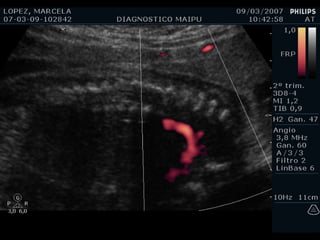

ECOCARDIOGRAFIA FETAL Modo B Modo M Doppler ¿CUANDO? A partir de la sem 12 por vía TV A partir de la sem 18 por vía abdominal Optimo: semana 22

Evaluación del corazón fetal en la ecografía obstétrica Modo B ¿CUANDO? Segundo y tercer trimestres ¿Como? De mayor a menor

EXAMEN BASICO EXTENDIDO Corte de 3 vasos Tracto de salida izquierdo Tracto de salida derecho